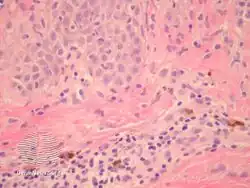

pathology-Prurigo pigmentosa -

pathology-Prurigo pigmentosa